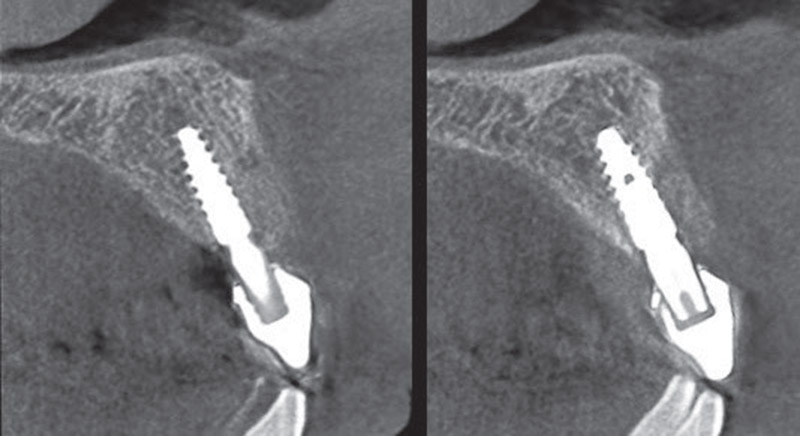

Viene applicata un innesto connettivale per mantenere il trofismo dei tessuti vestibolari ed una buona bozza alveolare (fig3-4). L’impianto viene protesizzato per 60 giorni con tecnica KiSS con conometria protesica utilizzando cappetta provvisoria in peek ribasando il provvisorio in pmma (fig.5).

Da notare aspetto tipico della protesi conometrica che non presenta irritazione da cemento, micro-movimenti a livello

dell’interfaccia implantare e stabilità dei tessuti (fig.6).

Fig. 3

Fig. 4

Viene applicata un innesto connettivale per mantenere il trofismo dei tessuti vestibolari ed una buona bozza alveolare (fig3-4). L’impianto viene protesizzato per 60 giorni con tecnica KiSS con conometria protesica utilizzando cappetta provvisoria in peek ribasando il provvisorio in pmma (fig.5).

Da notare aspetto tipico della protesi conometrica che non presenta irritazione da cemento, micro-movimenti a livello

dell’interfaccia implantare e stabilità dei tessuti (fig.6).

Fig. 3

Fig. 4